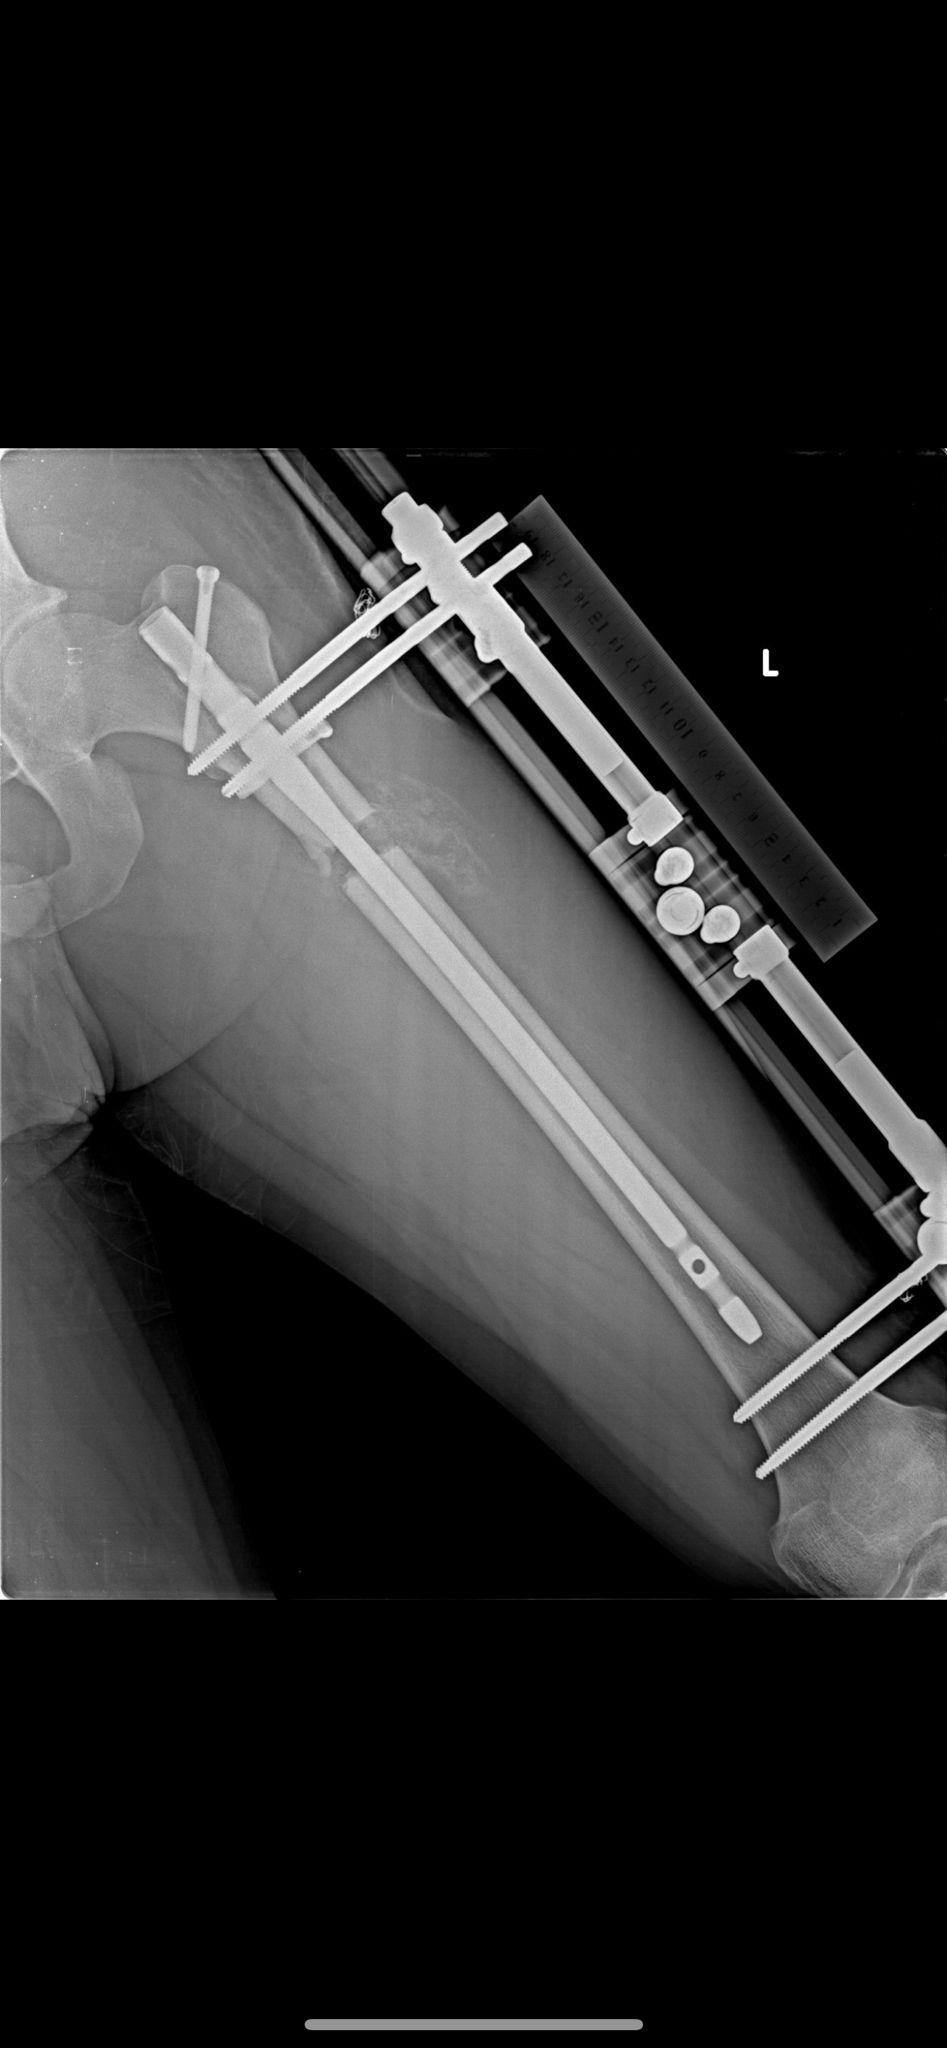

Yöntem ve Röntgen Görüntülerimiz

BAŞARILI SONUÇLARIMIZ

Boy uzatma ameliyatlarımızda kullandığımız modern yöntemlerin röntgen görüntüleri ve başarılı sonuçlarımızı inceleyebilirsiniz.

Fitbone Yöntemi

Fitbone® Yöntemi ile Boy Uzatma Tamamen İçten (Internal) Motorize Uzuv Uzatma Teknolojisi